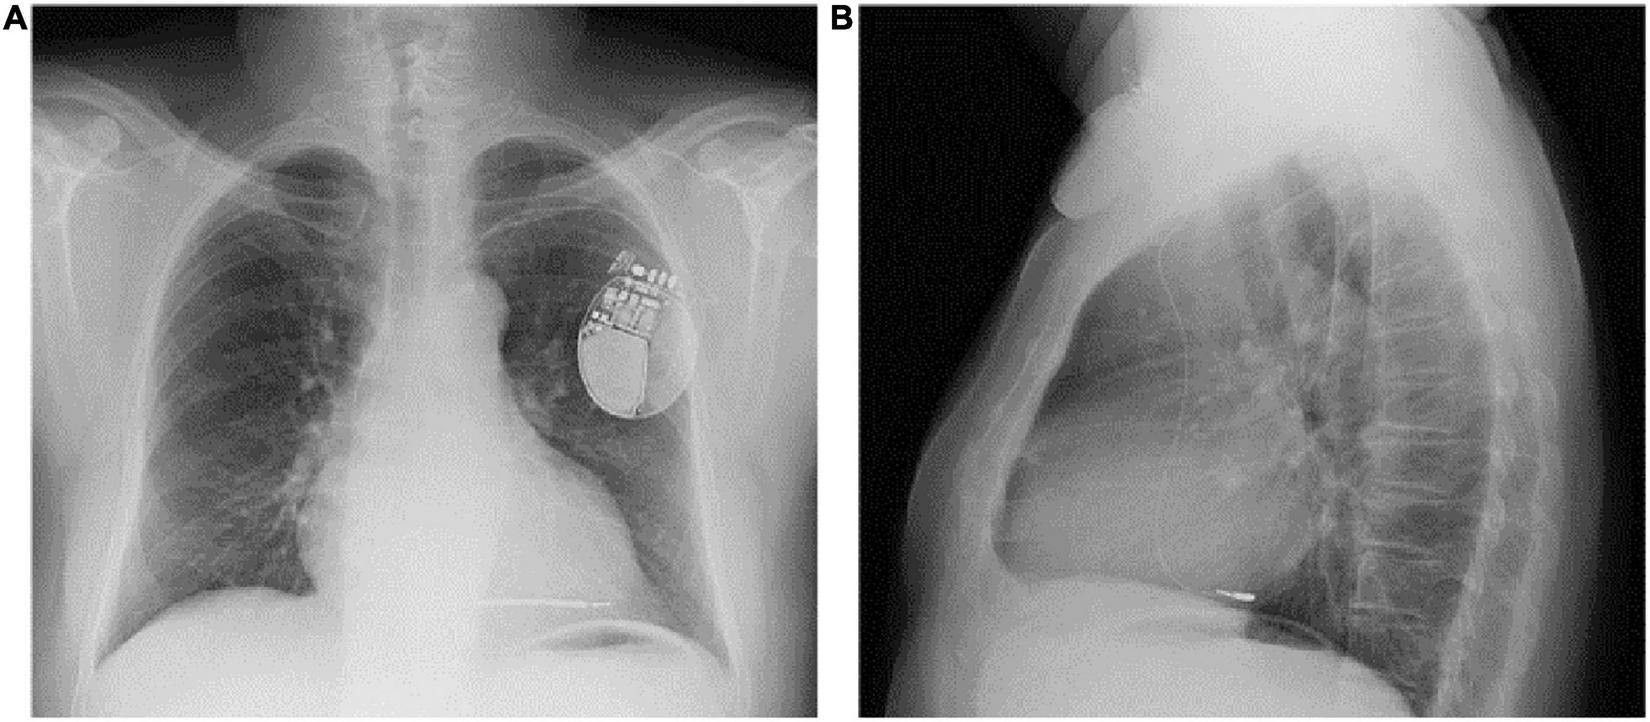

FIGURE 2

PA (A) and LL (B) chest x-ray of the patient showing inadvertent lead placement in the posterior branch of the coronary sinus. PA, posteroanterior; LL, laterolateral.

A 68-year-old Caucasian male was referred to our Arrhythmology and Electrophysiology Unit for lead revision of a single-chamber ICD implanted ten months earlier in another center. Two months before ICD implantation, the patient was hospitalized for symptomatic heart failure, NYHA class 3. A 12-lead ECG showed atrial fibrillation (AF) with rapid ventricular response. A transthoracic echocardiography (TTE) demonstrated reduced left ventricular ejection fraction (LVEF, 30%) and severe left atrial enlargement without significant valvular disease. An invasive coronary angiography (ICA) showed multivessel coronary artery disease (MVCAD) with a low Syntax score. Myocardial revascularization with percutaneous coronary intervention (PCI) and two drug-eluting stents (DES) implantation in the left anterior descendent (LAD) coronary artery and the obtuse marginal branch of the left circumflex was performed without complication. The patient was discharged on heart failure and rate-control therapy with a beta-blocker (bisoprolol 5 mg bid), an angiotensin receptor-neprilysin inhibitor (ARNI, sacubitril/valsartan 49/51 mg bid), a mineralocorticoid receptor antagonist (MRA), a loop diuretic, and digoxin (0.125 mg qd). After two months, because of persistent severe left ventricular systolic dysfunction, a single-chamber ICD with a single-coil passive fixation lead was implanted for primary prevention of sudden cardiac death (SCD). During subsequent follow-up, the patient was referred to our center for symptomatic PNS. At admission, the patient presented with mild dyspnea and mild ankle swelling. Blood tests were in the range of normality except for increased levels of N-terminal pro-B-type natriuretic peptide (NT-proBNP, 1,230 pg/ml, nr <125 pg/ml). Device control showed an excessive ventricular pacing percentage (about 15%) although ICD programming in VVI mode with a lower rate of 30 beats per minute, indicating phases of slow ventricular response with the necessity of ventricular pacing. PNS at very low energy output was also confirmed. Several symptomatic episodes of high ventricular rate (HVR) indicated an unsatisfactory pharmacological rate-control despite maximum tolerated drug dosage. Lead parameters were in the range of normality with a normal trend, thus excluding lead failure due to fracture or insulation defect. A 12-lead ECG showed AF with rapid ventricular response and normal QRS duration (90 ms) (Figure 1A). Unfortunately, a 12-lead ECG during ventricular pacing was not recorded before admission, however it was obtained during hospital stay from continuous ECG monitoring (Figure 1B). Paced QRS morphology showed a right bundle branch block (RBBB) pattern and superior axis. A chest X-ray (CXR) was obtained at admission (Figure 2). CXR showed a single-coil passive fixation defibrillation lead placed in coronary sinus posterior branch, thus explaining occasional PNS. Interestingly, the patient previously underwent two other CXR examinations but the incorrect lead placement was not recognized. A TTE was repeated and reduced LVEF without visualization of defibrillation lead in the right ventricle, in the absence of pericardial effusion, was confirmed. Lead explantation and CRT implantation for both high ventricular pacing percentage and predictable subsequent atrioventricular junction (AVJ) ablation for “ablate-and-pace” therapy were planned, because of reported suboptimal rate-control in patient history (alternance of slow and rapid ventricular response). A venogram was performed in order to confirm subclavian vein patency. A successful lead explantation with simple gentle traction using a non-locking stylet was performed. At the same time, we performed implantation of a CRT device with a single-coil active fixation defibrillation lead placed in the mid-ventricular septum, and a quadripolar passive fixation lead in coronary sinus posterior branch (the only available, Figure 3). The LV quadripolar lead was tested for PNS that was absent in pacing configurations excluding distal electrode, with optimal pacing threshold. Bedside echocardiographic examination ruled-out pericardial effusion. The patient was discharged the day after the procedure, and AVJ ablation was postponed after rate control evaluation at subsequent follow-up (Table 1).